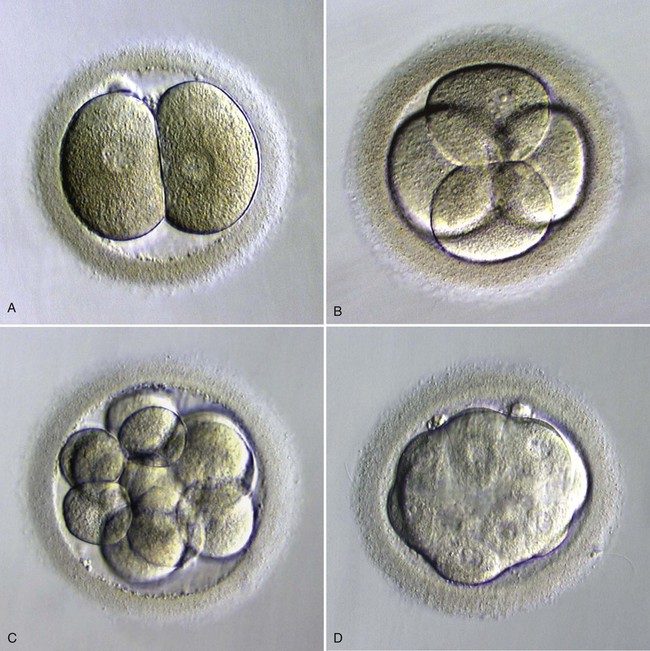

Бластоциста на 5 день — это стадия развития эмбриона, когда он уже начинает разделяться на клетки и приобретает важные структурные особенности. На этом этапе эмбрион представляет собой пузырёк с жидкостью, в котором находятся клетки, будущие части организма. На микроскопических фотографиях эта стадия выглядит впечатляюще, и изучение её позволяет понять, как развивается человеческий организм в самом начале. В этом материале мы собрали информацию о том, что происходит с эмбрионом на 5 день, а также полезные советы для тех, кто заинтересован в этой теме.

На 5 день эмбрион уже активно делится на клетки, формируя структуру, известную как бластоциста. Это важный этап для успешной имплантации в матку.

Визуально бластоциста на 5 день под микроскопом выглядит как пузырёк с жидкостью и группой клеток, которые постепенно организуются в будущие ткани.

Фотографии бластоцисты на 5 день помогают врачам и исследователям оценить качество эмбриона перед его возможной имплантацией.

Для получения точных результатов при изучении бластоцисты важно использовать высококачественные микроскопы, которые позволяют увидеть детали клеточной структуры.

Микроскопические изображения бластоцисты помогают медицинским специалистам исключить возможные аномалии и выбрать самые здоровые эмбрионы для трансплантации.

Если вы хотите лучше понять процесс развития эмбриона, фотографии бластоцисты на 5 день под микроскопом будут полезным визуальным материалом для изучения этой сложной темы.